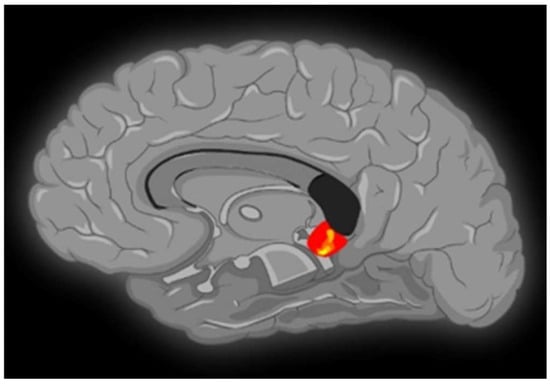

Contrasting minor with major melodies showed multiple activation sites (Figure 1) with the right parahippocampal gyrus (RPHG) being an eloquent brain area (Figure 2). Another discernible activation, when subjected to cluster-level correction, spanned both the left and right ventral anterior cingulate cortex (VACC) (BA 24) and extended into the left medial frontal gyrus (LMFG) within the medial prefrontal cortex (BA 10) (Figure 3). Remarkably, the inverse contrast (major over minor) did not yield significant activations. In a peak-voxel analysis, the response to the chromatic scale was intermediary when juxtaposed against the major and minor mode melodies for three of the aforementioned regions. These differential responses between the chromatic scale and melodies were not statistically significant, with an exception. Within the LMFG, the chromatic scale evoked the most prominent (least negative) response, trailed by the minor and subsequently the major mode. Notably, the contrast between the chromatic scale and the major mode was statistically significant in this context [25].

VACC activation is generally associated with affective processing, while its dorsal counterpart is linked with cognitive functions [26]. Moreover, the existing literature indicates that the VACC displays heightened sensitivity to emotional content characterized by negativity or sadness [27]. The observed engagement of the VACC might be consistent with the perception of minor mode melodies as possessing a sadder tonality in comparison to major melodies. Notably, prior neuroimaging research on mode-based contrasts has not reported VACC activation in contrasts between minor and major modes [28].

The detected involvement of the left medial frontal gyrus (LMFG) may be attributed to its robust neural connectivity with the anterior cingulate cortex and other limbic systems. Such a connectivity profile underscores the proposed function of the medial prefrontal cortex as an integrative nexus for emotional input from these associated regions [29].